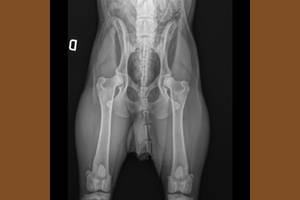

La displasia dell’anca e del gomito è una delle problematiche più conosciute nei cani di taglia grande dove il peso ed il rapido accrescimento evidentemente sono un'aggravante. Vi sono anche altri fattori che possono contribuire ed incidere sulla gravità ma alla base c'è comunque l'ereditarietà (che conta almeno per un 30%), per questo è fondamentale per un allevatore selezionare accuratamente i riproduttori, e per un futuro proprietario selezionare accuratamente l’allevatore, e diffidare da cucciolate improvvisare ove, seppur i cuccioli vengano ceduti con il pedigree, né i genitori né gli avi a monte sono stati controllati ufficialmente.

La displasia non è una patologia congenita, ovvero il cucciolo nasce sano, ma è una patologia dell’accrescimento: una serie di fattori che, agendo progressivamente nel tempo, possono arrivare nei casi più seri al blocco dell'articolazione. Quindi un cucciolo displasico è predisposto geneticamente alla patologia ma alla nascita, così come alla cessione dopo i 60 giorni, non è clinicamente malato; le sue componenti ossee, infatti, sono al momento normali nonostante la predisposizione genetica, che è necessaria per lo sviluppo della patologia. La sintomatologia clinica inizia generalmente dopo i 4 mesi o comunque entro l’anno di età, ma non è raro che la patologia diventi manifesta anche successivamente. Le terapie sono quasi sempre chirurgiche e successivamente fisioterapiche, con costi importanti e con una gestione del cucciolo davvero molto impegnativa e scadente dal punto di vista della socializzazione.